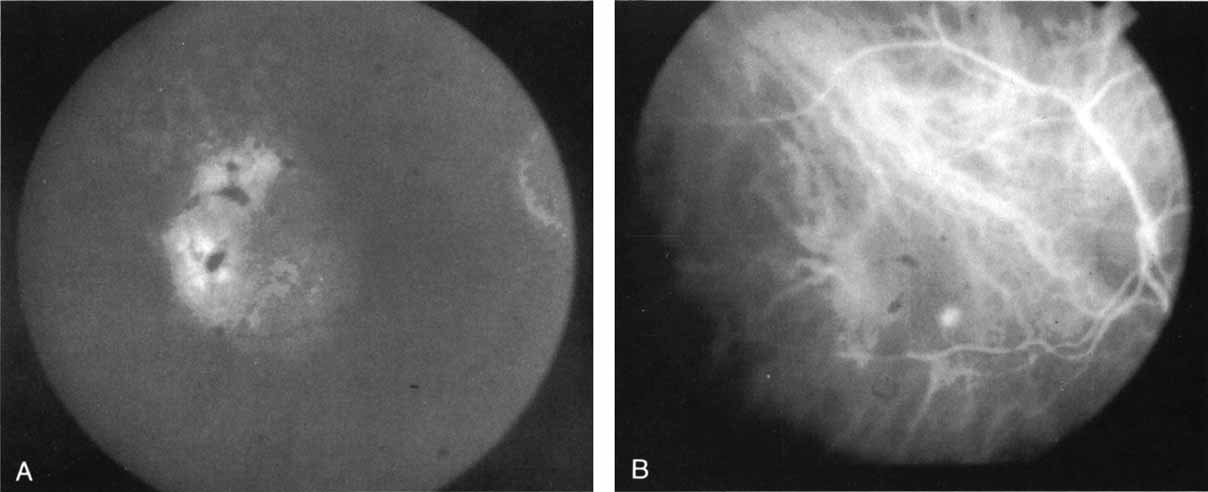

In a landmark article, Yannuzzi and associates18 demonstrated that ICG videoangiography was extremely useful in identifying well-demarcated localized areas of neovascularization in what had been classified as occult CNV by standard fluorescein angiography.19–24 In this study, 39% of 129 patients with “occult CNV” originally diagnosed as determined by fluorescein angiography were given a revised diagnosis of “well-defined neovascular lesions” based on the information obtained from the ICG study (Fig. 1). One study revealed that approximately 40% of patients with occult CNV diagnosed actually presented with early, well-defined focal areas of fluorescence on ICG videoangiography.25 They further defined two potential subgroups of occult CNV: those with and those without serous pigment epithelial detachments (PEDs) accompanying the occult neovascular process. They also pointed out that ICG angiography offered a potential advantage in identifying neovascular lesions when there was clinical evidence of recurrent CNV after previous laser photocoagulation treatment.

Subsequently, Yannuzzi and colleagues25 and Guyer and associates26 evaluated the usefulness of ICG angiography in identifying localized areas of CNV in patients with occult CNV with or without a serous PED. In a careful evaluation of more than 680 patients, they identified 22% of patients with localized lesions that might be amenable to laser therapy—lesions that would otherwise be classified as untreatable based on guidelines for laser photocoagulation (Figs. 2 and 3). As a result of this improved imaging technique, as many as two to three times the number of patients would have been potentially eligible for laser treatment than would have been treatable based on fluorescein angiography alone.